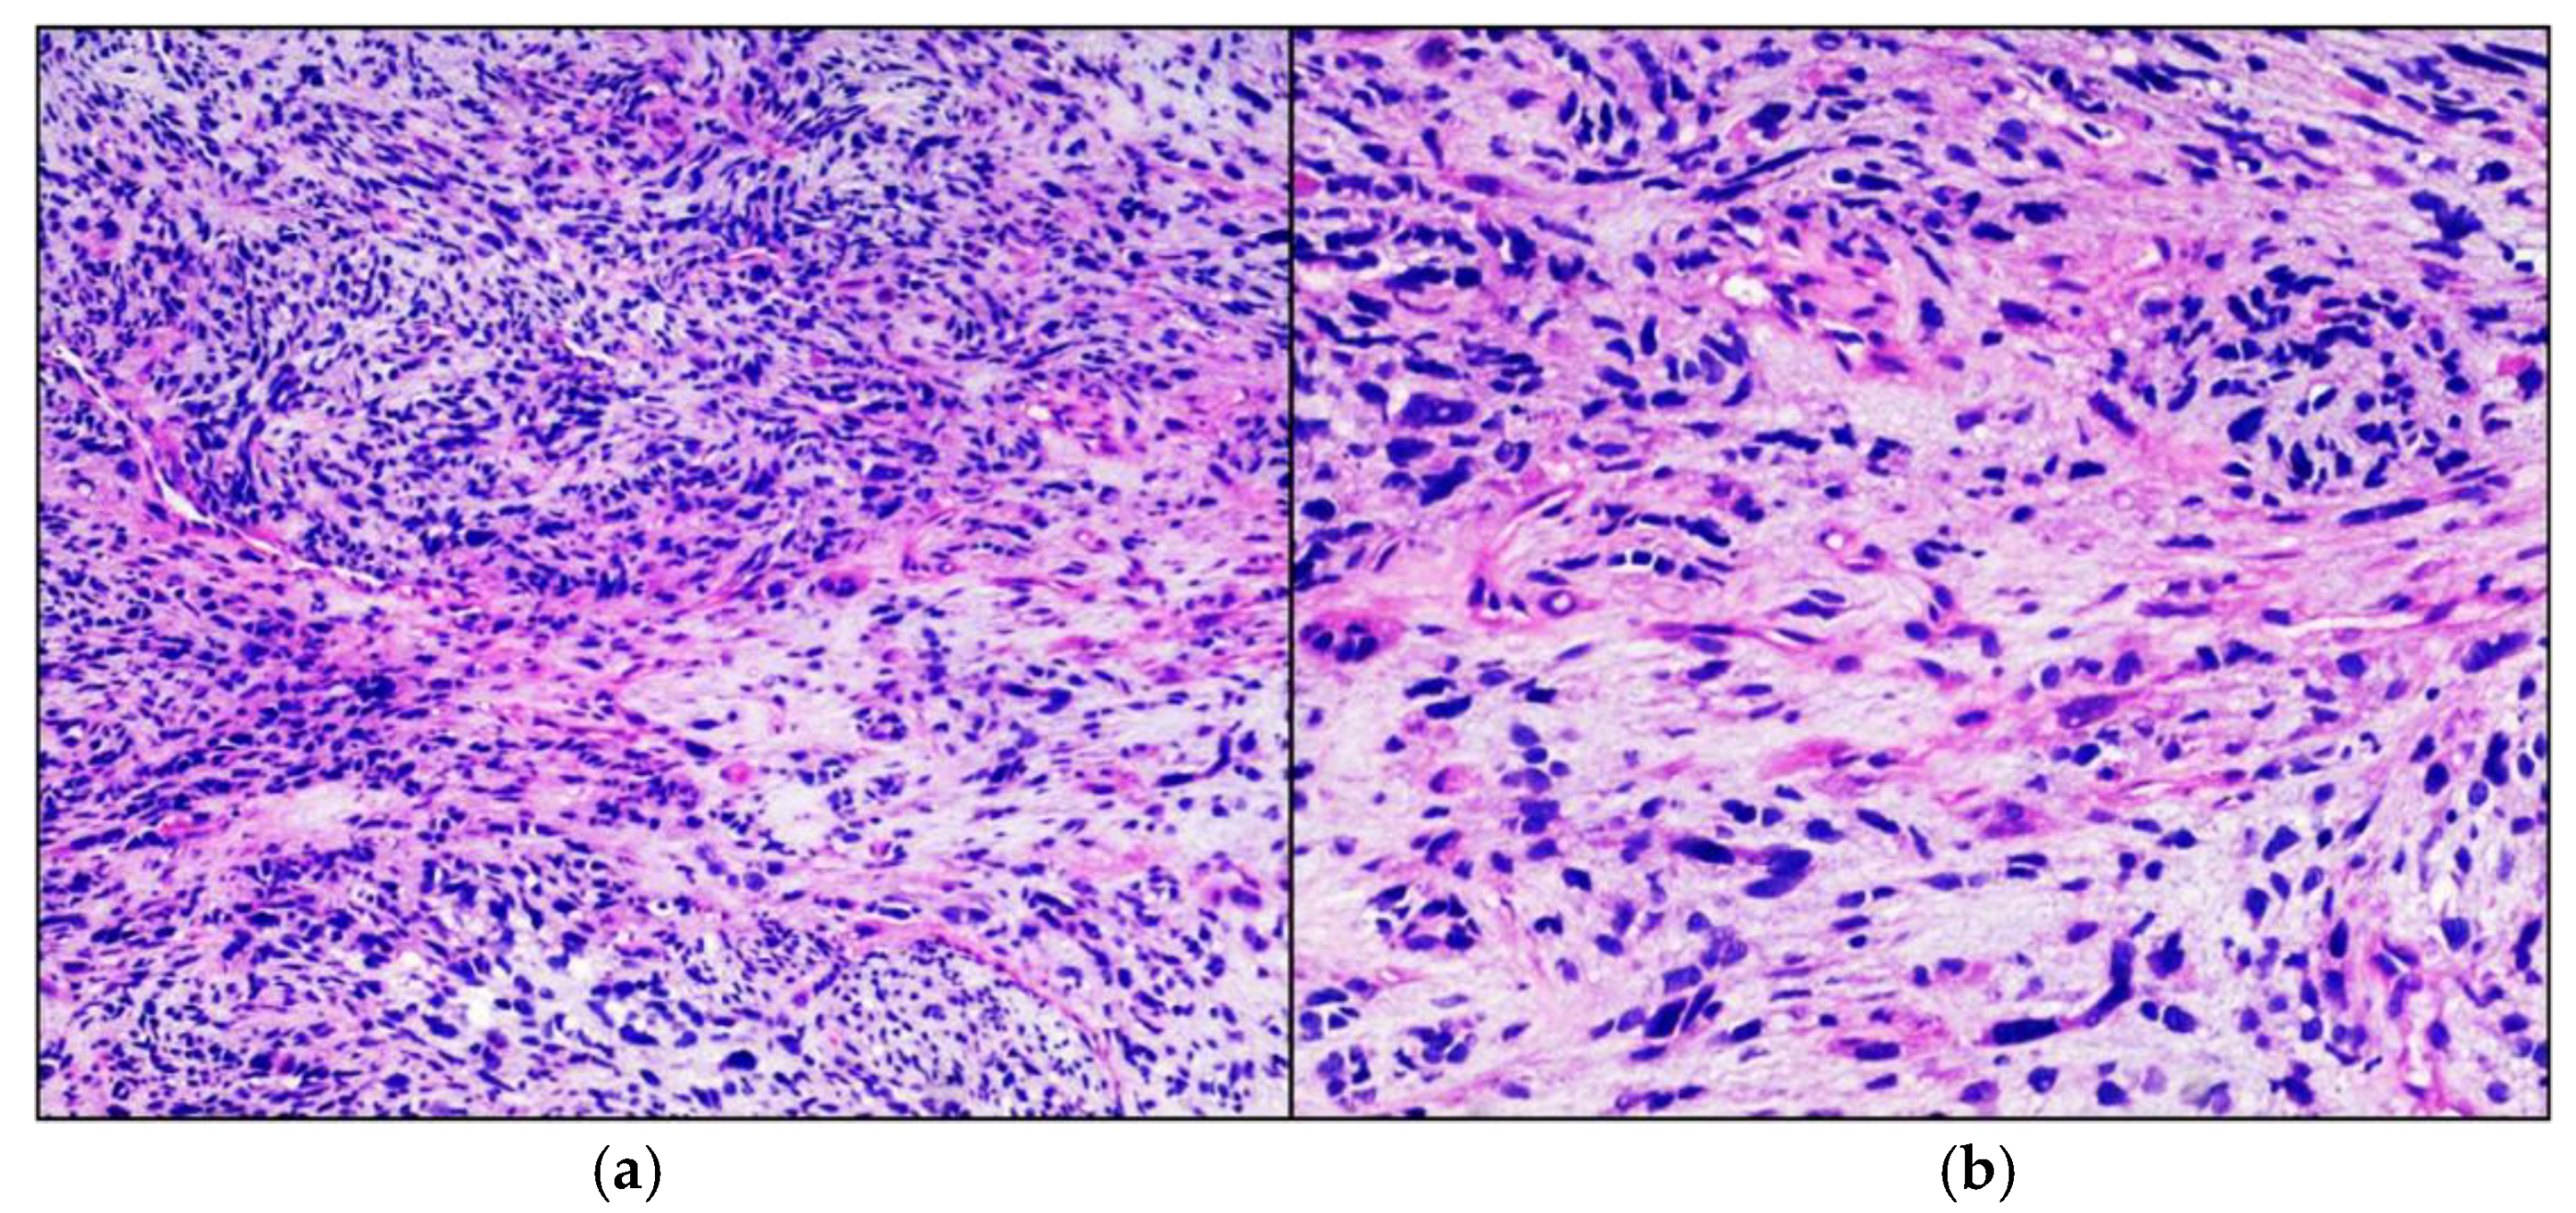

Figure 1.

Embrional Rhabdomyosarcoma. Hematoxylin-eosin stained photomicrographs, with original magnification 100× (a) and 200× (b), showing characteristic intersecting fascicle of spindle cells with eosinophilic cytoplasm and iperchromic pleomorphic nuclei.